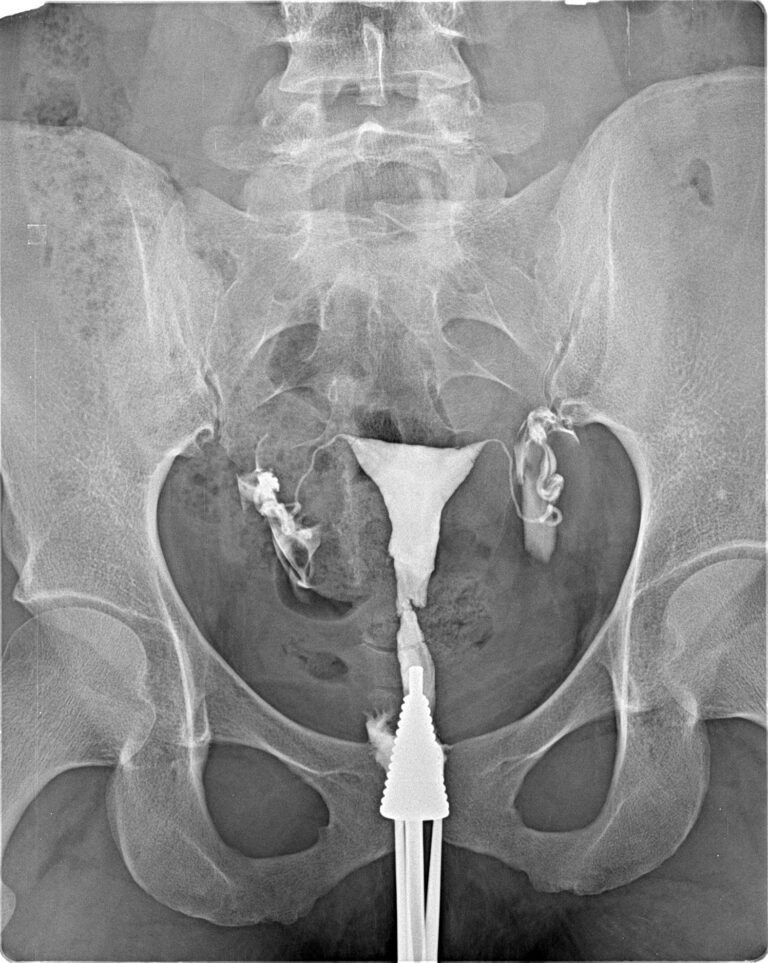

Exame radiológico que avalia o estado das trompas de Falópio e do útero, essencial para investigar dificuldades de concepção. A Histerossalpingografia é um exame radiológico